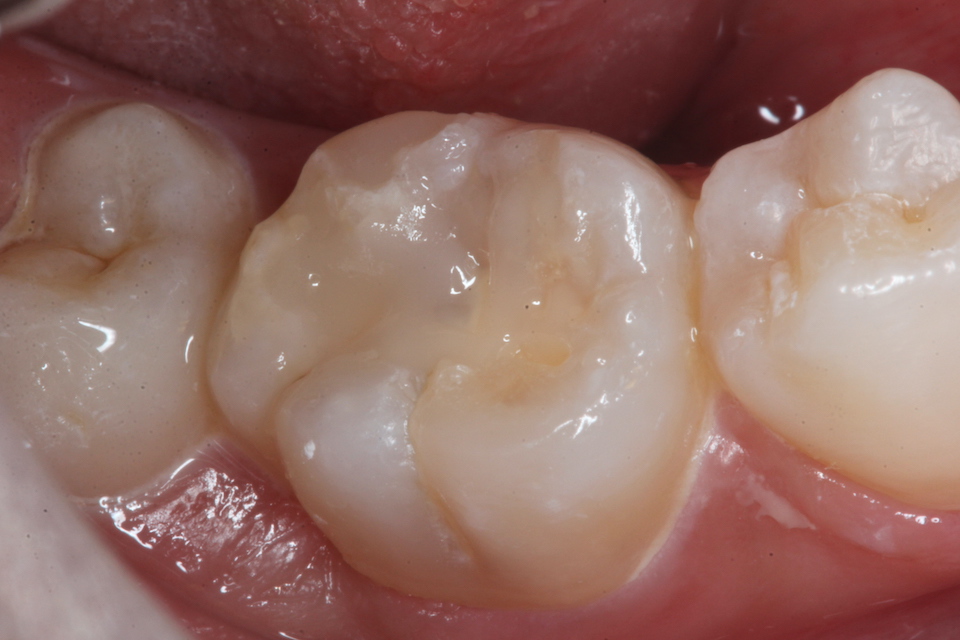

現在14歳女子、右下6、咬合面カリエス、咬合性外傷(食いしばり)、自覚症状なし

元々咬合面に深い溝や窩が歯の発生の過程でできることがあるのだが、そこから象牙質とエナメル質との間のイオン化傾向(自然電位)の差と虫歯の穴の中とその外部の間の酸素濃度差による起電力により虫歯が進行するタイプだ。

さらに外傷性咬合により微細なクラックがエナメル質に入り、虫歯の進行を助長する。